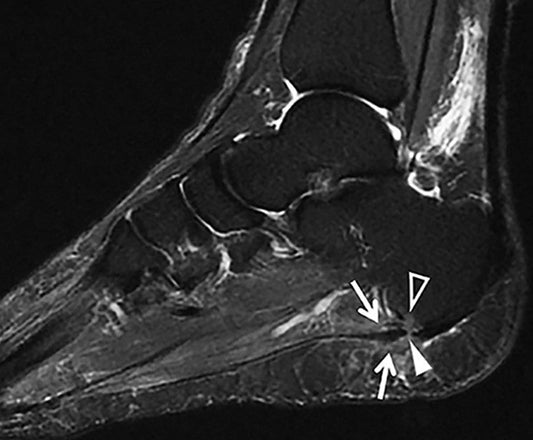

What is plantar fasciitis? Plantar fasciitis is one of the most common conditions causing heel pain. It involves inflammation of the plantar fascia — a tough, fibrous band of tissue...

Plantar Fasciitis